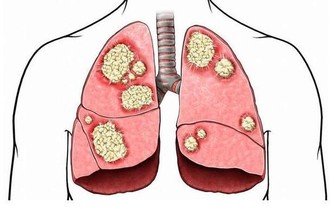

我國的中醫文化博大精深,中醫認為,人的身體一旦受了風寒,就會引起咳嗽,而咳嗽的人就不能夠吃寒涼的食物,這樣的話就會傷及到肺腑,而我們出現的咳嗽多數情況下是因為肺部的疾病引發的,因此,在咳嗽的時候千萬不要吃冷飲,如果吃了過多的寒涼之物,就會加重身體的疾病症狀哦!